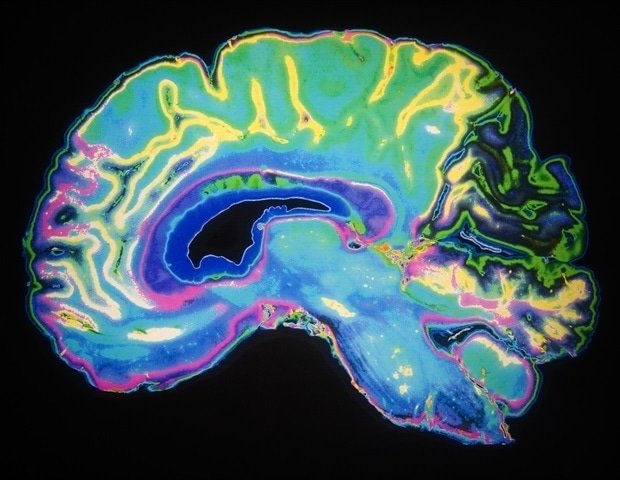

To support this blueprint, in a new study, Carlo Colantuoni, Ph.D., an adjunct professor of neurology at Johns Hopkins University and the Institute for Genomic Sciences at the University of Maryland School of Medicine, and other researchers gathered data from nearly 200 published studies and more than 30 million cells to advance insights into how the neocortex, the outermost layer of the brain, develops and forms over time. This area of the brain is responsible for a variety of functions, including how we think, sense, process and store information, and make decisions.

“Our goal is to understand how the neocortex is built at the cellular level and identify clues to developmental delays and early stages of brain disorders,” Colantuoni said. “By mapping the cellular transitions and genes that give rise to the neocortex’s complex structure and function, we will be able to better understand and attempt to treat diseases that occur in utero, in infancy, childhood, and even much later in life.”

In addition to mapping human models of the neocortex, the authors presented mammalian and mouse models. These various atlases demonstrate that gene expression programs that began as a spreading network millions of years ago have recently focused on human neural stem cells to drive expansion of the human neocortex. Researchers say this process contributes to and partially explains differences in high cognitive performance in humans compared to other animals.

The researchers also used the accumulated data to create a graph of neuron maturation in the human neocortex. This process has been prolonged over evolutionary time as the human neocortex and mental capacity expand. For example, this type of neural development takes weeks in mice but years in humans. This represents a sophisticated system difference that allows the human brain to learn how to adaptively interpret complex social, environmental, and sensory input over long periods of development.